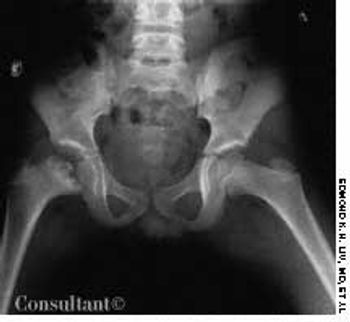

A 10-year-old boy presented with a limp and occasional pain in the right knee of 2 years' duration. A roentgenogram of the pelvis revealed fragmentation of the right capital femoral epiphysis with an irregular acetabulum.